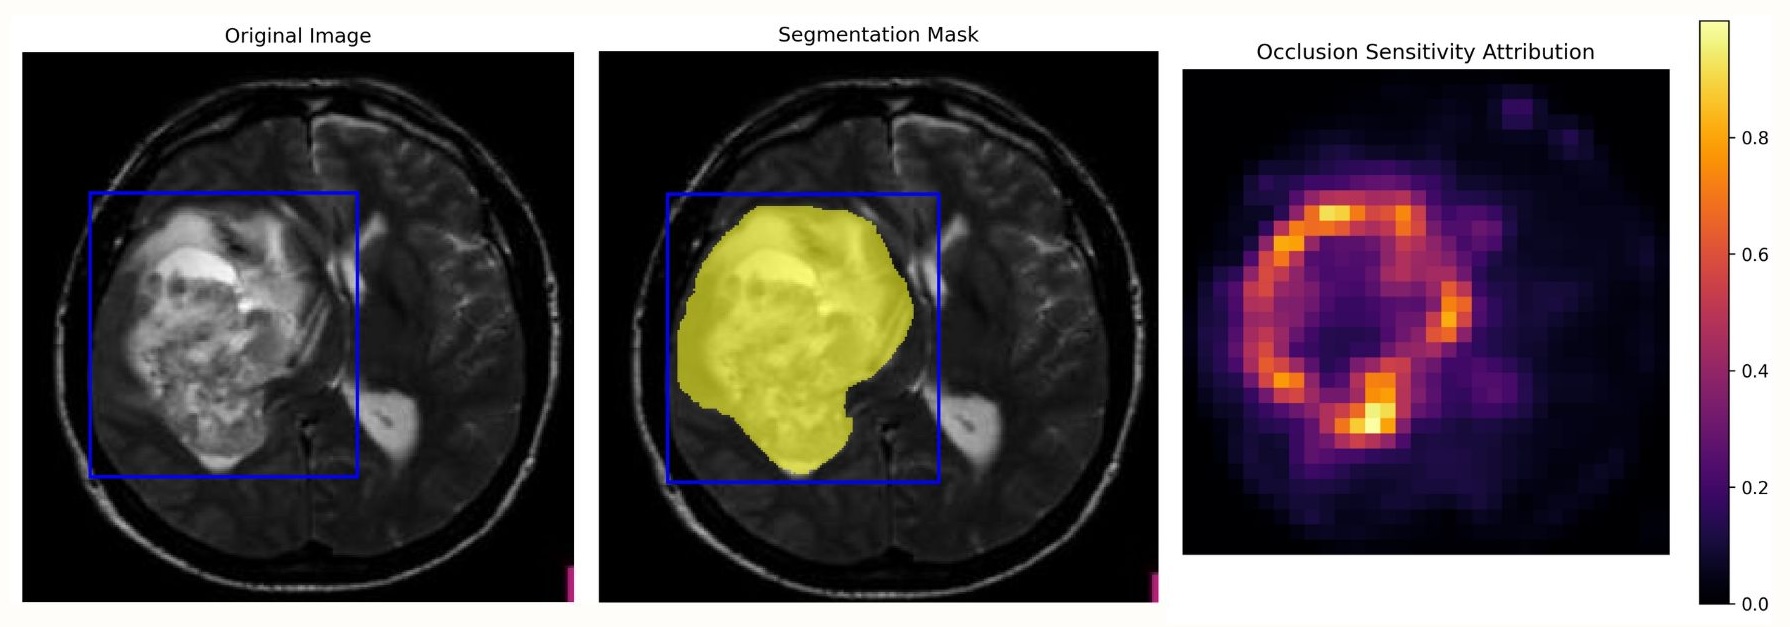

3.2.3 Occlusion Sensitivity Analysis

Occlusion Sensitivity assesses feature importance by systematically masking localized regions of the input image using a sliding window and measuring the resulting changes in the model’s output [45]. By iteratively occluding different spatial locations and quantifying their impact on the segmentation predictions, the method produces an importance map that highlights regions critical to the model’s decision process. This straightforward perturbation strategy offers intuitive and easily interpretable explanations and was found to be particularly effective for multi-layer medical imaging data, where the localized occlusion mechanism provides clear insights into the spatial dependencies learned by the segmentation model as shown in Fig 5.

3.5 CLIP-guided Perturbation-based Explainability

The selective application of perturbation-based explainability methods is designed to address a key limitation of such approaches, namely their high computational cost. By restricting perturbations to regions of interest (ROIs) identified through vision-language-guided localization, the explainability process reduces redundant computations while concentrating analysis on clinically meaningful areas. This region-guided strategy significantly decreases the number of patches that must be evaluated, leading to improved runtime efficiency without sacrificing interpretability. For implementation, we employ MedSAM, a medical adaptation of the Segment Anything Model, to generate segmentation masks that serve as the basis for attribution analysis. To ensure seamless integration with perturbation-based explainability frameworks, we introduce a MedSAMWrapper class that encapsulates the model’s forward pass and standardizes its interface for compatibility with custom perturbation routines. Selective occlusion sensitivity is then performed by occluding the input image using patches with a stride of 32, while explicitly skipping patches that do not intersect with the binary ROI mask. For each retained patch, segmentation is recomputed and the change in Dice score relative to the unperturbed baseline is measured to quantify attribution. These attribution scores are accumulated to form a sensitivity map, which is subsequently normalized for visualization. Overall, this selective perturbation scheme substantially reduces computational overhead and yields more focused, anatomically aligned explanations by confining analysis to clinically relevant regions.

3.5.1 Occlusion-based Anatomical Region Extraction

Our anatomical region extraction strategy is built upon a selective occlusion sensitivity framework that concentrates computational effort on clinically relevant anatomical structures. To achieve this, we employ a wrapper-based implementation that preserves the original segmentation model architecture while enabling seamless integration with perturbation-based explainability pipelines. This design ensures compatibility with downstream analysis modules without altering the underlying model behavior, while maintaining spatial consistency and contextual awareness during perturbation.

As shown in Fig. 6, the central contribution of this framework is the introduction of ROI-guided importance masking, in which binary or grayscale region-of-interest masks defining anatomically relevant areas are first thresholded to obtain binary representations. These masks are then resized to match the model input resolution using nearest-neighbor interpolation to preserve hard anatomical boundaries and avoid interpolation-induced artifacts. The resulting ROI masks serve as spatial constraints that guide the perturbation process, ensuring that explainability analysis remains focused on meaningful anatomical regions rather than background or irrelevant areas.

Building on this representation, we implement a selective patch processing strategy based on a sliding-window occlusion scheme using pixel patches with a stride of 32 pixels. Unlike conventional occlusion sensitivity analysis, patches are processed only if they overlap with the ROI mask, effectively filtering out non-informative regions. This selective mechanism reduces the number of evaluated patches from approximately 10,000 in full-image analysis to between 500 and 2,000 patches, depending on the size of the ROI and the applied importance threshold (e.g., retaining the top 20% most relevant regions). As a result, the proposed strategy achieves a computational reduction of approximately 75-95% while preserving the fidelity of the resulting explanations. The accumulated perturbation responses are aggregated into occlusion heatmaps that highlight anatomically significant regions by quantifying the impact of localized occlusions on segmentation performance, as shown in Fig. 7.

As shown in Fig. 8, XAI-CLIP consistently delivers substantial computational efficiency gains across all evaluated perturbation-based explainability methods. In particular, the XAI-CLIP-Occlusion variant achieves pronounced runtime reductions of 250 seconds on Machine A and 214 seconds on Machine B, corresponding to efficiency improvements of 62.3% and 69.4%, respectively. When integrated with LIME, XAI-CLIP further demonstrates significant computational savings, reducing the total cost to 94,431 GFLOPs, which represents a 28.4% reduction relative to the baseline implementation. The RISE-based XAI-CLIP variant similarly exhibits notable efficiency gains, achieving 27-34% reductions in runtime alongside a decrease of 11,078 GFLOPs (6.1%), underscoring the effectiveness of ROI-guided perturbation in reducing computational overhead without compromising explanatory capability.

Similarly, as shown in Table 3, using occlusion sensitivity as the underlying perturbation strategy for XAI-CLIP resulted in the most pronounced performance gains among all evaluated methods. Quantitatively, this configuration achieved improvements of 44.6% in Dice coefficient and 96.7% in Intersection-over-Union relative to conventional occlusion-based explanations. These gains are further supported by qualitative assessment, which reveals substantially reduced noise, sharper boundary delineation, and improved spatial coherence in the generated saliency maps when compared to baseline approaches as demonstrated in Fig. 10.